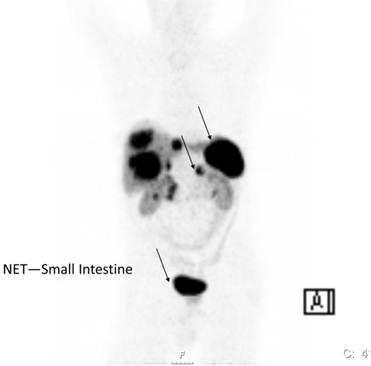

Somatostatin receptors are G-protein coupled membrane glycoproteins at the moment five subtypes of human somatostatin receptors have been cloned.[4] The somatostatin analogs octreotide and lanreotide bind with high affinity to receptor subtypes 2 and 5. The expression of somatostatin receptor type 2 is present in 70-90% of NETs. Therefore radioactive labelled somatostatin analogs allow the visualisation and staging of these tumors expressing somatostatin receptors 2 and 5. The most commonly used radioligand is 111In-DTPA-octreotide (Octreoscan) recently co-registration with CT has been implemented in nuclear medicine.[6-8] This new fusion technique allows better interpretation of the imaging finding with better anatomical localisation (Figure 1).

Figure 1

Functioning imaging of neuroendocrine tumors using [111In]DTPA-octreotide (SPECT) and CT scanning from a patient with a malignant metastatic pancreatic endocrine tumor.

The ability to tag somatostatin analogs with 68Ga has revolutionized the role of PET in diagnosis, staging and therapy monitoring of patients with receptor positive NETs. One of the advantages of the 68Ga-DOTANOC/DOTATOC PET or PET/CT study over 111In-Octreotide scintigraphy is better visualisation of lesions which are difficult to be seen on planar or SPECT imaging.[11-13] 68Ga- DOTATOC PET appears to be superior especially in detecting small tumors or tumors bearing only low density of SRS (Figure 2). In general 68Ga-DOTATOC or DOTANOC PET is able to pick up many lesions which could not be picked up by CT-scan. It is of significance in therapy monitoring and is a useful adjunct in deciding the amount of radioactivity to be administered for PRRT. In an intraindividual study comparing the diagnostic efficacy of 68Ga-DOTANOC and 68Ga-DOTATATE, 68Ga-DOTANOC is superior to 68Ga-DOTATATE in terms of sensitivity.[14] In summary, among several advantages of 68Ga-somatostatin analogs over 111In-DTPA Octreotide scintigraphy higher sensitivity is present.[15] It is a one-stop procedure, the patient can leave the clinic after 1 hour instead of coming back 4 and 24 hours for scanning. It will also in the future be cheaper than SRS.

Figure 2

68Ga-DOTA-Octreotide PET/CT scanning with a patient with malignant carcinoid tumor showing multiple lymph node metastases as well as large liver metastases.